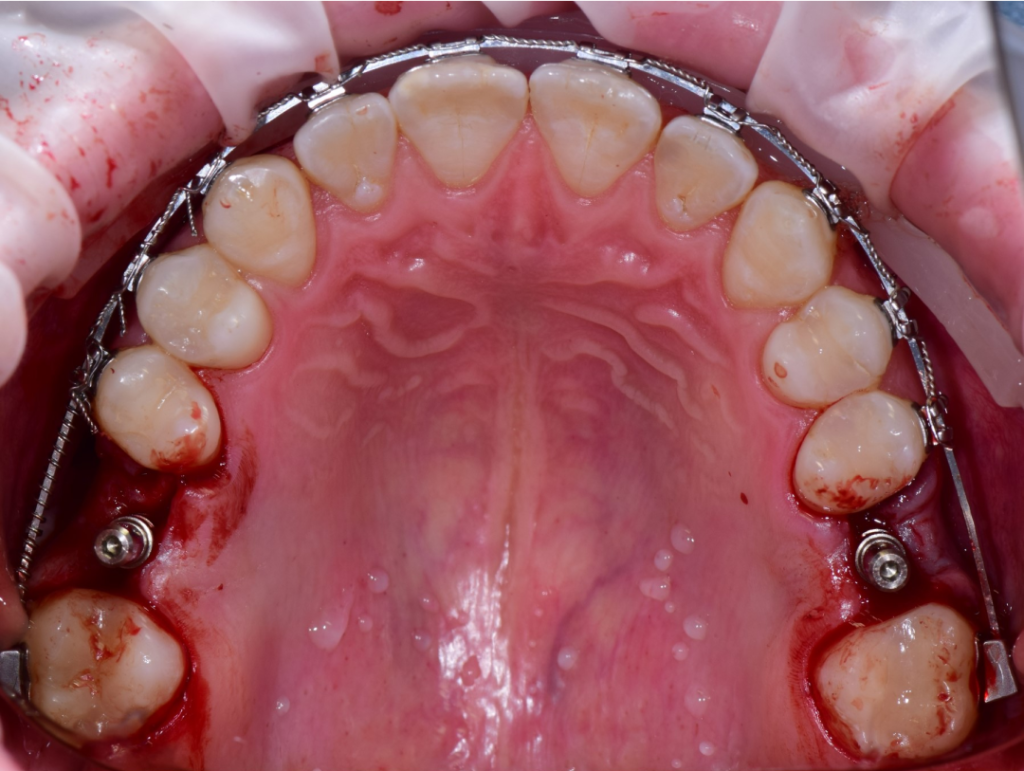

По результатам диагностики принято решение провести синус-лифтинг с помощью боров SinPro. В ходе вмешательства установлены имплантаты AnyRidge и AnyOne с первичной стабилизацией 40 Ncm.